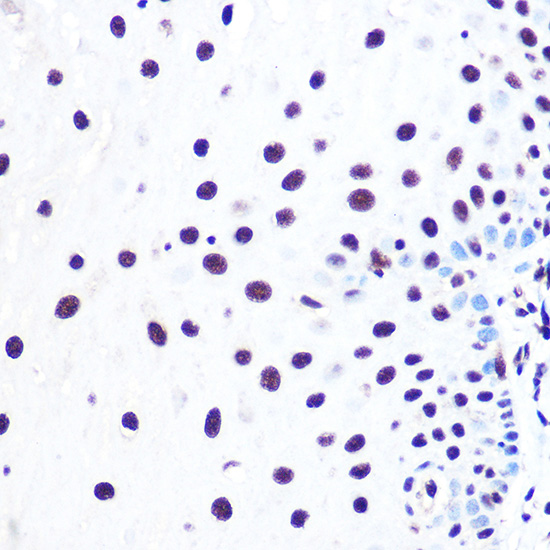

Immunohistochemistry of paraffin-embedded rat pancreas using NELFE Rabbit pAb.

Immunohistochemistry of paraffin-embedded human esophageal using NELFE Rabbit pAb.

Immunohistochemistry of paraffin-embedded mouse testis using NELFE Rabbit pAb.